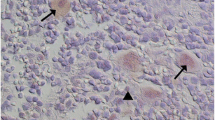

Tissue specimens were fixed in 4% paraformaldehyde solution and embedded in paraffin. Two specimens of every examined liver clippings were stained to determine the expression of ERα and ERβ. The analytical procedure has been described previously (Gajęcka et al. 2021; Singhai et al. 2011).

Optical density (scanning) of stained slides—the expression of ERα and ERβ in liver samples from both groups was analysed in scanned slides (Pannoramic MIDI Scanner, 3DHISTECH, Budapest, Hungary) using the NuclearQuant program (3DHISTECH, Hungary). Scanned slides were converted into digital images (Figs. 1 and 2). Nuclear immunoreactivity was evaluated. The nucleus detection profile was as follows: radius—1.50–2.10 µm, minimum nuclear area—0.9 µm, minimum circularity—3, smoothness—1. ERα and ERβ expression was evaluated on a 4 point scale: negative = 0 [0], weak and homogeneous = + [1], mild or moderate and homogeneous = + + [2], intense or strong and homogeneous = + + + [3]. Staining intensity was evaluated on the following scale: from 0—none of the below, + average intensity < 190 (CD BrownInt), + + average intensity < 170 (CD BrownInt), + + + average intensity < 100 (CD BrownInt) (Gajęcka et al. 2021). The results were expressed by the average percentage of hepatocytes with ERα and ERβ expression.

Optical density—Brown staining in the scanned slides (Figs. 1 and 2) was not specific, and it could have occurred during non-specific tissue staining analyses examining the expression of ERα and ERß in hepatocytes tissues stained with DAB (non-specific light brown staining was observed in most specimens).

The effect of 42-day exposure to DON, ZEN and MIX on the expression of selected ERs was determined in hepatocytes in four groups on the basis of a 4-point rating scale, which was used in the text. (negative—[0]; weak and homogeneous—i.e. one + as [1]; mild or moderate and homogeneous—i.e. one + + as [2]; intense or strong and homogeneous—i.e. one + + + as [3]). Due to the large number of significant and highly significant differences, the results for hepaticytes are presented not only in tabular form.

ERα expression at level [0] was excited more intensely in each date in the CON group compared to the ZEN, DON and MIX groups (Fig. 1, Table 2). In the CON group, significant differences in ERα expression were found at different absorption levels (strongest in level [0], and at the other levels they were more muted), but absorption was significantly strongly accentuated in dates II and III (especially in the DON and MIX groups). Significant differences in ERα expression were also noted at other absorption levels. The obtained values were much lower than those recorded at the absorption level [0]. In the CON group, mean ERα expression was highest at the level of staining [0] and increased with subsequent exposure dates.

Analysis of immunohistochemical expression of ERα documents that it was significantly elevated in DIII in the DON and MIX groups (in [1], [2] and [3] gradients scale) (Fig. 1, Table 2). In the DON group and partly in the MIX group, ERα expression at the absorption level [3] was statistically higher than in the other experimental groups. Differences in ERα expression at levels [1], [2] and [3] were observed in all groups of experience over time and especially in the DON and MIX groups. As in the CON group, excitation of ERα expression + was observed in the ZEN and DON groups at the absorption level [0] in DIII compared to DI, while at the absorption level [3], ERα expression was more excited in the DON group in DII and DIII, and in the MIX group in DIII, compared to the CON and ZEN groups. Gene expression was stronger in the [0] experimental groups only in DI and DII. As mycotoxin exposure continued, statistical differences were more and more frequently observed between experimental groups.

In the CON group, immunohistochemical ERß expression was muted on all gradients scale and in all DI-DIII (Fig. 2, Table 2), as well as in the MIX group. Mean ERß expression values in all experimental groups and at all exposure times, the expression was most strongly expressed (also statistically) at the absorption level [3]. The greatest silencing was found at the absorption level [0], the observed differences were not always significant. Immunohistochemical analysis of ERß expression in the liver compared to ERα expression yielded completely different results. In the experimental groups, ERß expression was more excited at the absorption level [3]. Statistical differences between the experimental groups were found at all exposure dates, alternating in DI in the DON and MIX groups, in DII in the ZEN and DON groups, and in DIII in the CON and MIX groups. The above situation can be explained by the fact that in addition to the tested xenobiotics, other factors had to act, such as the ongoing change in oestrogen clearance, biotransformation processes and the formation of metabolites whose biological activity is much longer in the exposed organism, or environmental factors.

There was a clear presence of a trend. In the case of ERα (Table 2), all groups have the highest number of negative receptors. Only in the DON group, similar expression values were found on the [0] scale, defined as negative, and on the [3] scale, defined as intense or strong. On the other hand, ERβ (Table 2) was expressed on a scale equal to [3], determined as intense or strong, in all groups of the experiment and at all exposure times. It could be suggested that the mycotoxins under study, on the one hand, silence the expression of ERα, and on the other hand, more abundant expression of ERβ genes takes place. However, it should be noted that an analogous situation occurs in the CON group.